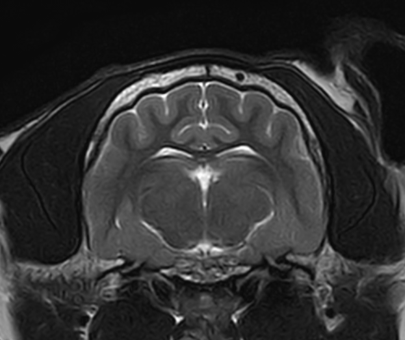

3T MRI

기존 본원에서 이용하던 1.5T 장비와 비교하여 높은 해상도와 빠른 스캔 시간(촬영 부위 당 30분 미만)으로 MR 촬영 시 환자의 마취 부담을 줄일 수 있습니다.

3T MRI는 국내 동물병원에서 최상급 촬영 장비에 해당하며 본동물의료센터의 MRI는 3T MRI 중에서도 하이엔드급 장비(Philips Ingenia)를 사용하고 있습니다.

소뇌 경색(개)

01뇌 MRI

· 뇌신경계 질환의 정확한 감별 및 조기진단

· 뇌수두증, 뇌출혈, 뇌종양, 뇌수막염, 소뇌탈출 등

· 전정계(중이, 내이) 질환의 진단